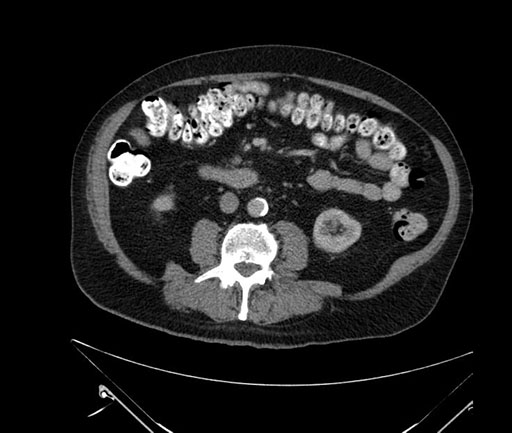

Whipple (pancreaticoduodenectomy) [case 7]

Imaging Analysis

Look through the patient's CT scan to identify any areas of concern for the necessary procedure.

Based on your CT findings, which issue(s) would give reason for "planned slowing down moment(s)" in this case?

Considering a standard Whipple procedure, what step(s) of the operation would you do differently in this case?